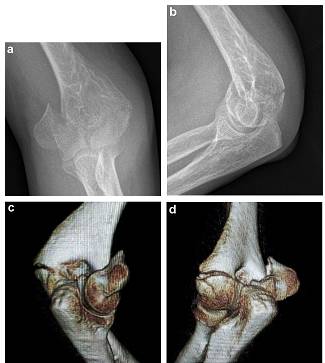

标准肘关节正侧位片对完全骨折诊断意义重大,正位片中肱骨远端位于前侧,但是对于肘关节疼痛患者难以获得。由于患者肘关节疼痛和骨折移位,X线检查可能无法有效确定骨折粉碎程度。如果肘关节处于半屈曲位,可能无法采用CT扫描。对此,作者通常采用在手术室全麻下牵引前臂行X线检查,同时可复位一些骨折块和获得满意度的肱骨远端视角(图1)。

图1,C型完全关节内骨折(双髁骨折),a,正位片,b,外侧位片,c,牵引下正位片,d,牵引下外侧位片,e,后入路TRAP技术,f,锁定加压钢板前临时固定,g,固定后X线检查。